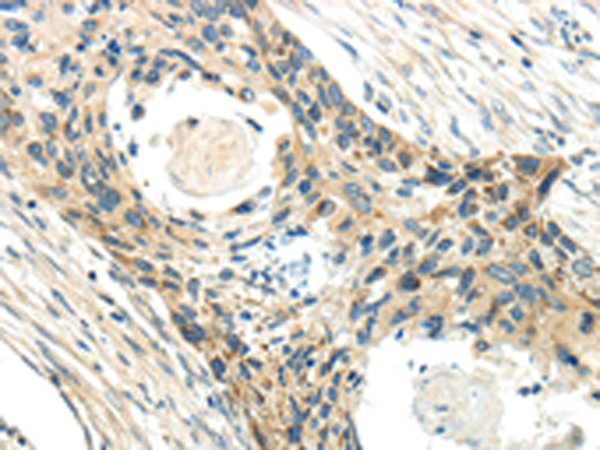

分类: 科研抗体货号: P10714别名: NS5ATP1应用: IHC反应种属: Human, Mouse, Rat